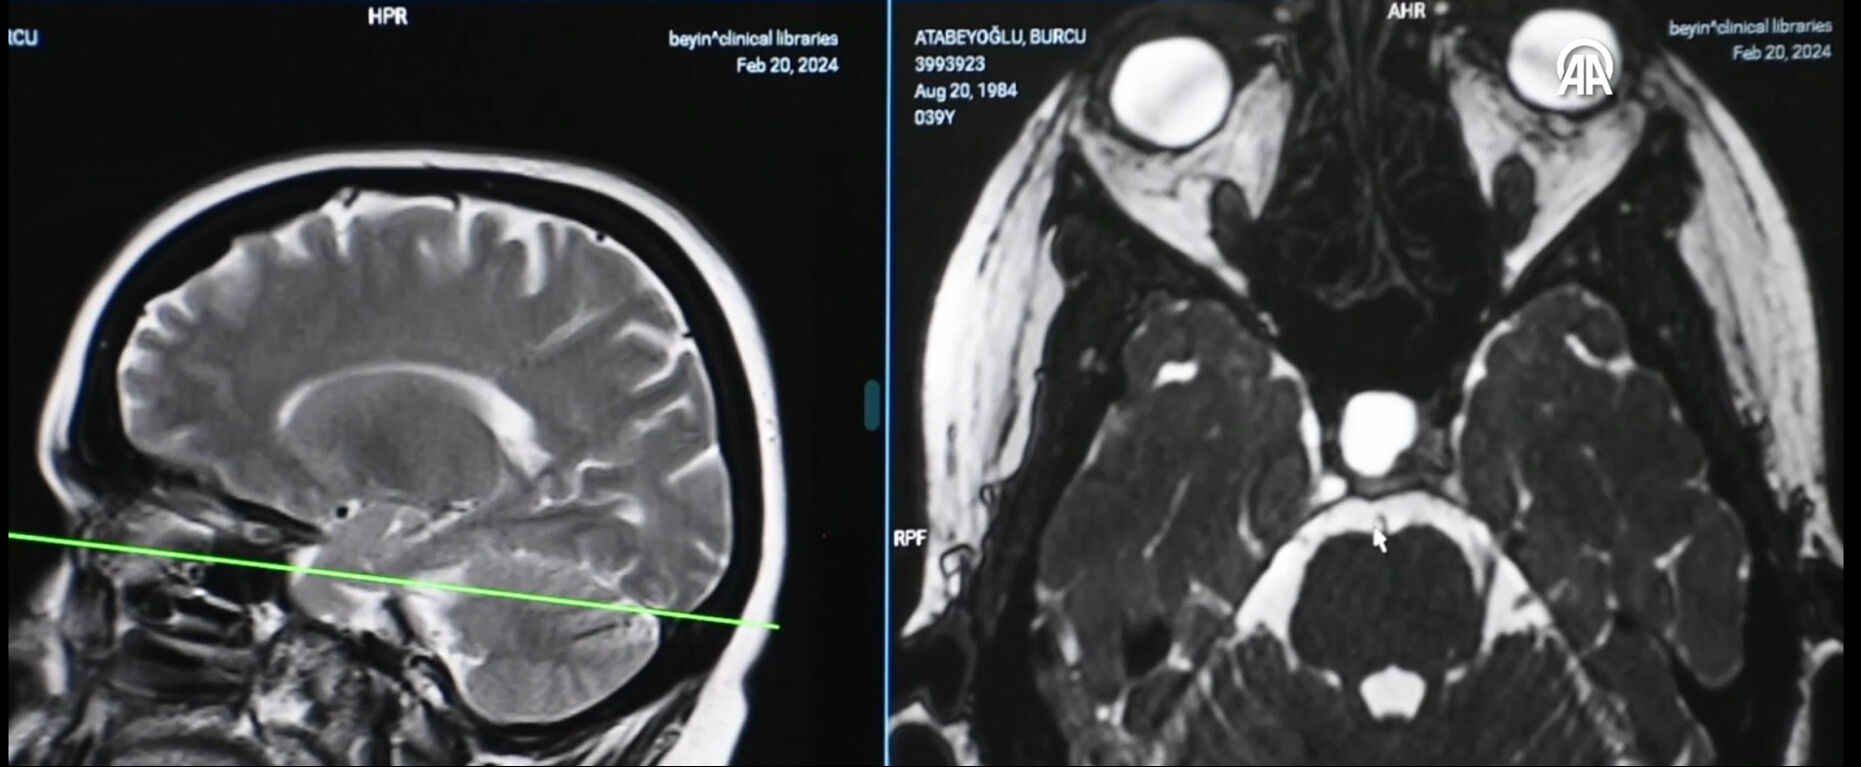

Topsakal, hastalığın genel itibarıyla birçok sebepten oluşabildiğine dikkati çekerek, "Beyindeki bir damarın sinire değmesi sonucunda oluşabilmektedir. Hastalar bu şikayetler için öncelikle ilaçla takip edilirler ama fayda görmeyen hastalarda eğer çektiğimiz MR ve tetkiklerde durumu uygunsa ameliyatla bu hastalığı tedavi edebiliyoruz." dedi.

Atabeyoğlu'nun tetkiklerinde de ağrının, bir damarın sinire değmesi sonucu oluştuğunun tespit edildiğini anlatan Topsakal, şöyle devam etti:

"Bu ameliyat, Trabzon'da ve Doğu Karadeniz Bölgesi'nde ilk defa yapıldı. Ameliyattan sonra Burcu hanım fayda gördü, süreci de güzel geçirdi. Sonrasında semptom, atak ya da şikayeti geçekleşmedi. Hastamız da biz de memnun ve mutluyuz. Ameliyat sırasında kulak arkasından beyne girerek, beyinciğe yakın bölgedeki damar ve siniri birbirinden ayırıyoruz. Bu işlem yaklaşık 3 saat sürdü."